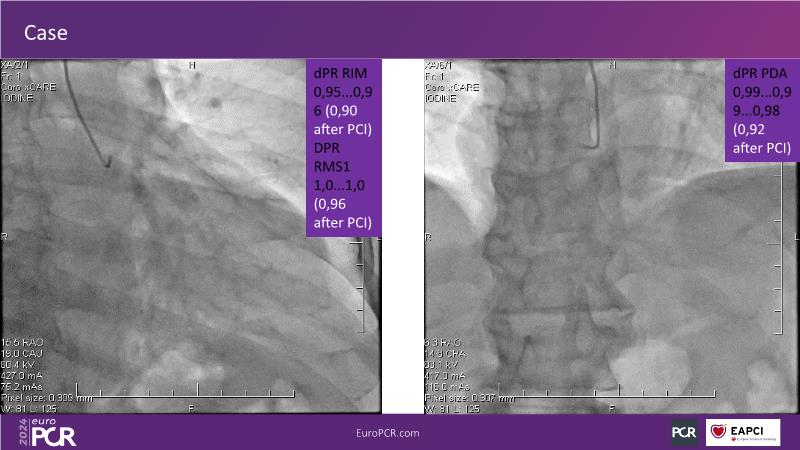

Follow this session to discover how accurate resting index can inform decision-making for DCB in CTO patients and understand the role of physiology in a new PCI workflow for complex MVD. Thus, you will learn about a DCB intention-to-treat strategy guided by post-PCI coronary physiology in complex lesions, review new procedural techniques and workflows from real-world cases, and explore the pros and cons of this novel approach.

- To learn about DCB intention-to-treat strategy guided by post-PCI coronary physiology in complex lesions

- To review new procedural technique and workflow from real world patient cases